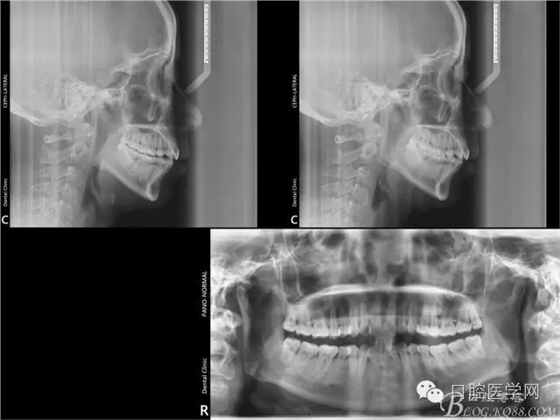

這是一例比較常見的前突伴擁擠的拔牙矯正病例。常規(guī)拔除四顆第一雙尖牙。使用活動翼唇側(cè)一步法矯正技術(shù)進行矯正。以下是矯正三個月效果。

初診照片